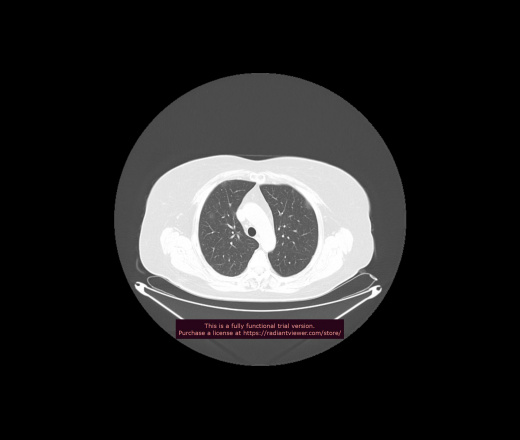

Уважаемые коллеги, если имеется интерес, сможете ли Вы спрогнозировать дальнейшее +-одинаковое течение процесса у 4 данных разных пациентов? Зацепиться где-то можно очень просто, где-то нельзя.